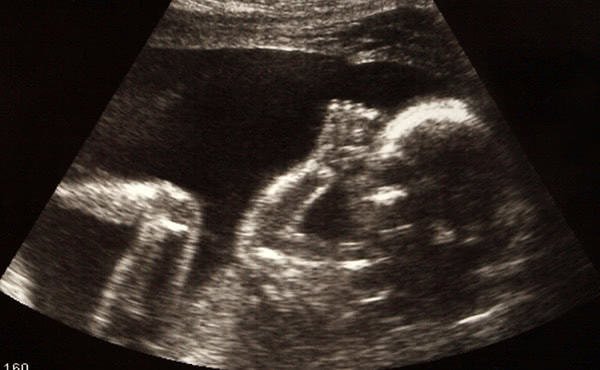

A la segona, tot era normal, però a la tercera, el ginecòleg li va dir que un dels fetus no era viable per tenir l’urèter totalment obstruït. Un altre col·lega li va confirmar el diagnòstic i va comentar que el millor era eliminar-lo en benefici de l'altre fetus.

Van consultar un altre especialista, i va dir que podia ser un quist, però que amb les ecografies el primer diagnòstic semblava correcte. En una nova consulta, l'opinió va ser la mateixa, encara que l'obstrucció podria ser parcial.

Des del principi vaig acudir a l’Eduardo, perquè la meva nora també és metge i em semblava que m’escoltaria. L'embaràs va seguir endavant, tot i que hagué de fer molt de repòs. Per fi, un mes abans del previst van néixer dos belles criatures: un nen (el del miracle) i una nena. Agraeixo a l’Eduardo aquest favor que ha omplert d'alegria la família.